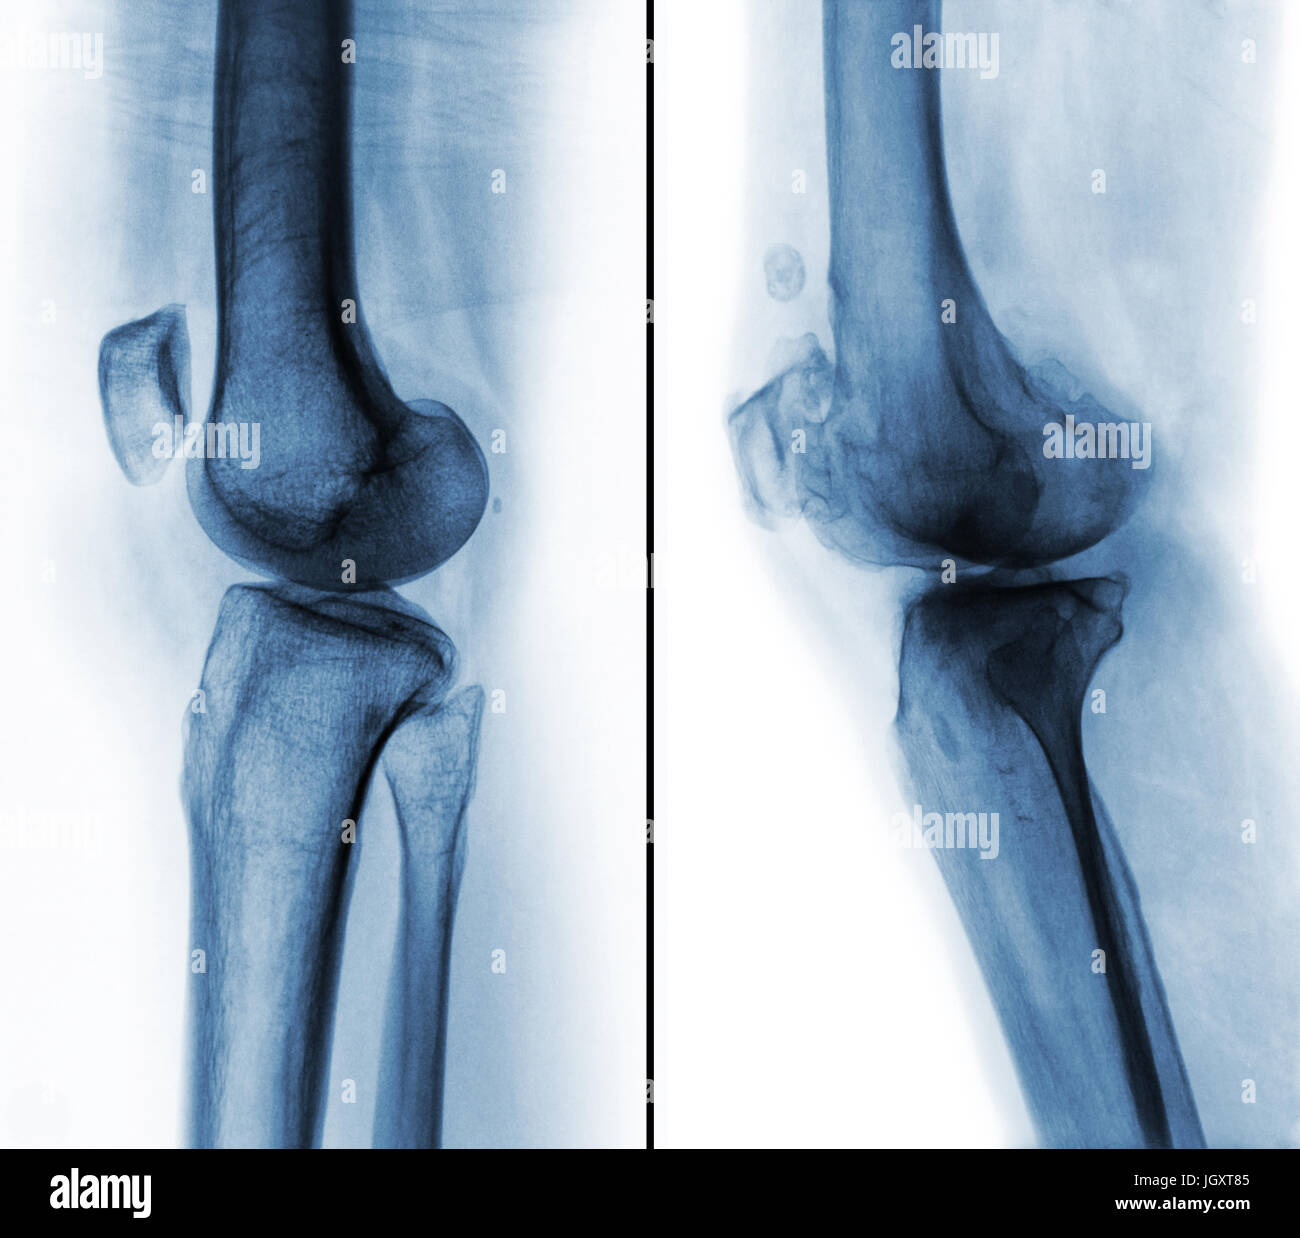

Comparaison entre le genou humain normal ( image de gauche ) et de l'arthrose du genou ( image de droite ) . Vue latérale . Banque D'Imageshttps://www.alamyimages.fr/image-license-details/?v=1https://www.alamyimages.fr/photo-image-comparaison-entre-le-genou-humain-normal-image-de-gauche-et-de-l-arthrose-du-genou-image-de-droite-vue-laterale-148107237.html

Comparaison entre le genou humain normal ( image de gauche ) et de l'arthrose du genou ( image de droite ) . Vue latérale . Banque D'Imageshttps://www.alamyimages.fr/image-license-details/?v=1https://www.alamyimages.fr/photo-image-comparaison-entre-le-genou-humain-normal-image-de-gauche-et-de-l-arthrose-du-genou-image-de-droite-vue-laterale-148107237.htmlRFJGXT85–Comparaison entre le genou humain normal ( image de gauche ) et de l'arthrose du genou ( image de droite ) . Vue latérale .

Comparaison entre le genou humain normal ( image de gauche ) et de l'arthrose du genou ( image de droite ) . Vue latérale . Banque D'Imageshttps://www.alamyimages.fr/image-license-details/?v=1https://www.alamyimages.fr/photo-image-comparaison-entre-le-genou-humain-normal-image-de-gauche-et-de-l-arthrose-du-genou-image-de-droite-vue-laterale-148107296.html

Comparaison entre le genou humain normal ( image de gauche ) et de l'arthrose du genou ( image de droite ) . Vue latérale . Banque D'Imageshttps://www.alamyimages.fr/image-license-details/?v=1https://www.alamyimages.fr/photo-image-comparaison-entre-le-genou-humain-normal-image-de-gauche-et-de-l-arthrose-du-genou-image-de-droite-vue-laterale-148107296.htmlRFJGXTA8–Comparaison entre le genou humain normal ( image de gauche ) et de l'arthrose du genou ( image de droite ) . Vue latérale .

Comparaison entre le genou humain normal ( image de gauche ) et de l'arthrose du genou ( image de droite ) . Vue latérale . Banque D'Imageshttps://www.alamyimages.fr/image-license-details/?v=1https://www.alamyimages.fr/photo-image-comparaison-entre-le-genou-humain-normal-image-de-gauche-et-de-l-arthrose-du-genou-image-de-droite-vue-laterale-148107261.html

Comparaison entre le genou humain normal ( image de gauche ) et de l'arthrose du genou ( image de droite ) . Vue latérale . Banque D'Imageshttps://www.alamyimages.fr/image-license-details/?v=1https://www.alamyimages.fr/photo-image-comparaison-entre-le-genou-humain-normal-image-de-gauche-et-de-l-arthrose-du-genou-image-de-droite-vue-laterale-148107261.htmlRFJGXT91–Comparaison entre le genou humain normal ( image de gauche ) et de l'arthrose du genou ( image de droite ) . Vue latérale .

Comparaison entre le genou humain normal ( image de gauche ) et de l'arthrose du genou ( image de droite ) . Vue latérale . Banque D'Imageshttps://www.alamyimages.fr/image-license-details/?v=1https://www.alamyimages.fr/photo-image-comparaison-entre-le-genou-humain-normal-image-de-gauche-et-de-l-arthrose-du-genou-image-de-droite-vue-laterale-148107279.html

Comparaison entre le genou humain normal ( image de gauche ) et de l'arthrose du genou ( image de droite ) . Vue latérale . Banque D'Imageshttps://www.alamyimages.fr/image-license-details/?v=1https://www.alamyimages.fr/photo-image-comparaison-entre-le-genou-humain-normal-image-de-gauche-et-de-l-arthrose-du-genou-image-de-droite-vue-laterale-148107279.htmlRFJGXT9K–Comparaison entre le genou humain normal ( image de gauche ) et de l'arthrose du genou ( image de droite ) . Vue latérale .